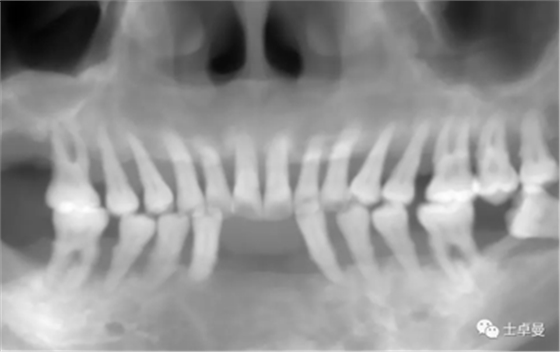

影像學(xué)檢查

CBCT檢查:顯示口內(nèi)余留牙牙槽骨吸收至根尖1/3;

上頜雙側(cè)后牙區(qū)上頜竇底可用骨高度不足;

下頜雙側(cè)后牙區(qū)下頜神經(jīng)管上方可用骨高度不足。